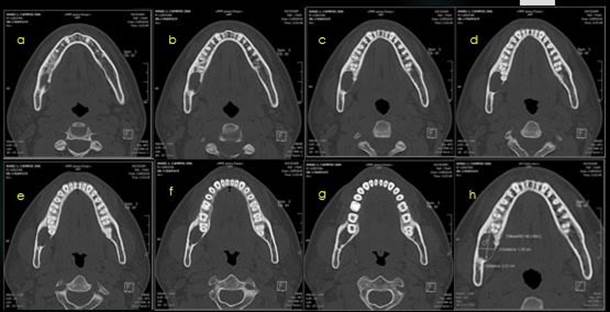

-          Examen imagienológico: de tipo tomografía axial computarizada.

Figura. 1. Ortopantomografía inicial, hallazgo ocasional. Fuente Palima (2016).

Componente hipodenso, con destrucción de la cortical superior de la hemimandibula derecha, ubicado en la Ud. 48, quedando las raíces del mismo sumadas a la lesión, tiene un diámetro de 2.5 x 2.2 x 1.3 cm y densidad del tejido solido de 66UH. Se plantea TU óseo  primario de hemimandibula, sin embargo no se descarta proceso infeccioso de tipo absceso de evolución crónica, y afectación del canal mandibular, asociado a la lesión.

Sse procede a evaluar y analizar ortopantomografia inicial, lo cual hace referencia a una lesion de 1,7 cm x 2cm aproximadamente ya que esto es referencial, evaluación de imágenes de TAC,  analisis de informe imagienológico,       exámenes     de laboratorio que arrojan leve aumento de la serie blanca asociada a infección, ya con todos estos datos clinicos e imagienológicos, se  procede a la discusión y planificacion quirúrgica en la que se decide su remocion  completa y no parcial, realizar estudio histopatológico esperando los resultados bajo conducta espectante si amerita un segundo tiempo quirúrgico.

Figura 4.  Ortopantomografia con medidas estimadas del tamaño de la lesión. Fuente Palima (2016).